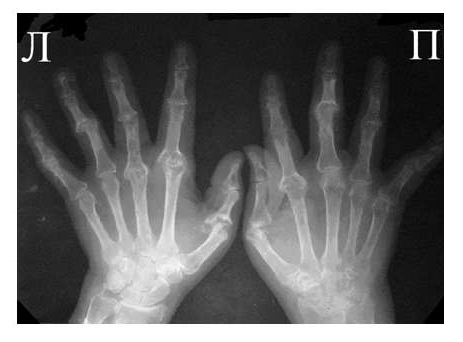

Одним из главных отличительных признаков ревматоидного артрита (РА) от других заболеваний является симметричность изменений мелких суставах кистей и стоп, которые становятся суставами-«мишенями» в первую очередь и поэтому именно эти области изучаются для определения стадии заболевания. Наиболее часто используемой в повседневной практике рентгенологической классификацией является деление ревматоидного артрита на стадии по Steinbrocker в различных модификациях.

Рис. 3 Сочетание ревматоидного артрита и остеоартроза

Большинство ошибок встречаются при начальных стадиях, особенно при начале РА в пожилом возрасте и сочетании его с остеоартрозом (см. рис. 3). В этом случае для подтверждения диагноза РА и предупреждению случаев его гипердиагностики служит выявление симметричных эрозий в типичных для ревматоидного артрита суставах (запястья, плюснефаланговые, пястно-фаланговые).